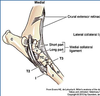

______ Collateral Ligaments have both a Short and Long Portion

Tarsus